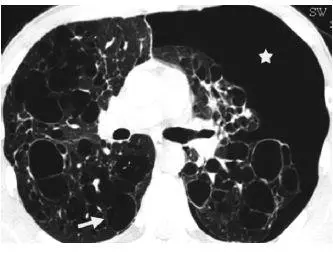

早期疾病薄层断层扫描(CT)可显示1–10mm的小叶中心结节或者空洞(图1)。随着病情的发展,囊性病变逐渐取代结节,表现为厚或薄壁囊腔,形态多不规则(图2)。结节和囊性病变通常累及双肺上中野,肺尖和肺底以及肋膈角常不受累。约25%的患者由于胸膜下囊腔破裂导致自发性气胸,累及双侧并且可以反复发作,这是本病的首发症状(图3)。终末期疾病的特点是肺过度充气以及广泛的囊腔,形成终末期肺气肿(图4)。薄层CT具有特征性人口统计学分布特点及临床表现,是PLCH临床诊断的重要依据,从而避免肺活检。在儿童中,薄层CT表现与成人相似,但更病变更广泛(图5),并且与未发现与吸烟有关的病灶。

图3 25岁男性PLCH患者。薄层CT横轴位显示双肺上叶大小不等的不规则囊变(箭头),左侧气胸(☆)